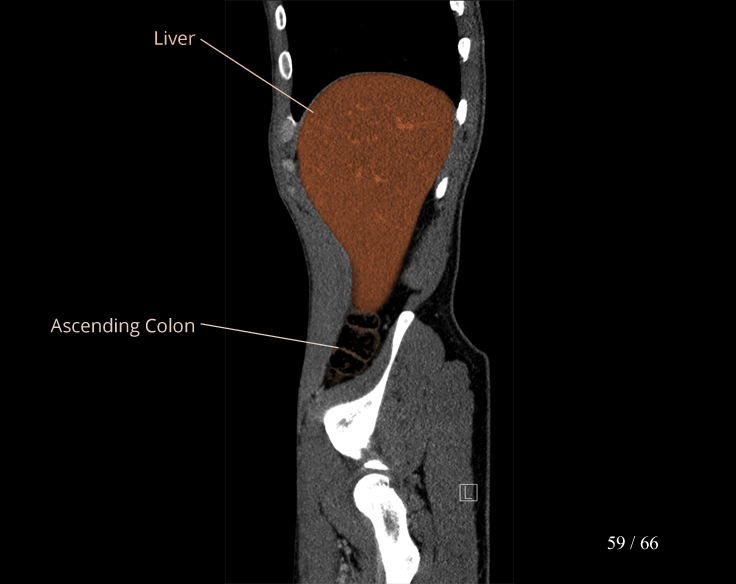

Body

Covers abdominal CT anatomy.